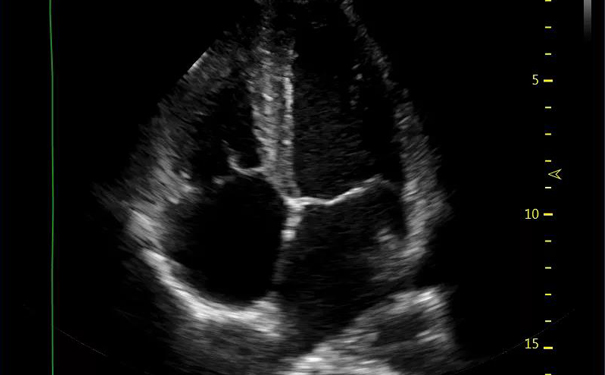

心脏的结构就像一座四开间的二层小楼,分为左右心房和左右心室。

飞依诺彩超四腔心切面

四腔心切面